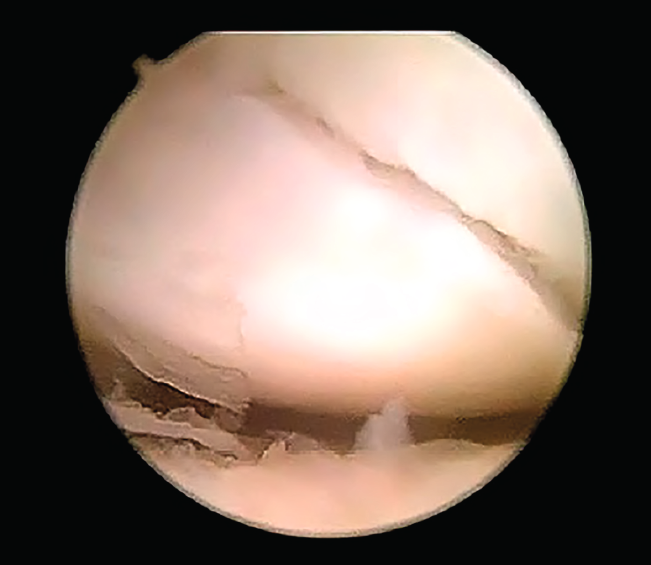

Figura 9. Reducción de fragmento distal con gancho palpador introducido por portal mediocarpiano radial; visión desde el portal mediocarpiano ulnar.

Una vez que se ha comprobado la colocación de la aguja, se realiza la medición de la longitud del tornillo, se avanza la aguja guía hacia volar para permitir la extensión de la muñeca, minimizando el riesgo de rotura del material. A continuación, a través de los portales MCR y MCU se verifica la reducción obtenida de la fractura; si no se ha conseguido una reducción aceptable, se retira por volar la aguja dejándola en el fragmento distal; a continuación, se procede a la reducción de los fragmentos de forma indirecta, mediante manipulación e hiperextensión de la muñeca o utilizando agujas de Kirschner a modo de joysticks para movilizar los fragmentos, o de forma directa, manipulando el fragmento distal con un gancho palpador o con un periostotomo que se introducirán por el portal MCR (Figura 9).